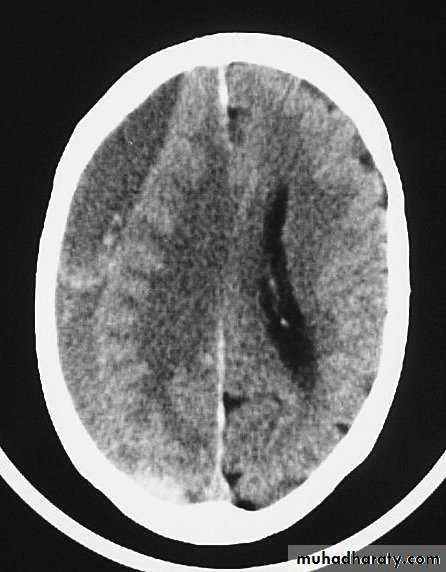

CT scans demonstrates contusions as small areas of haemorrhage in the cerebral parenchyma.

3. Cerebral Contusion

Resolution of Contusion